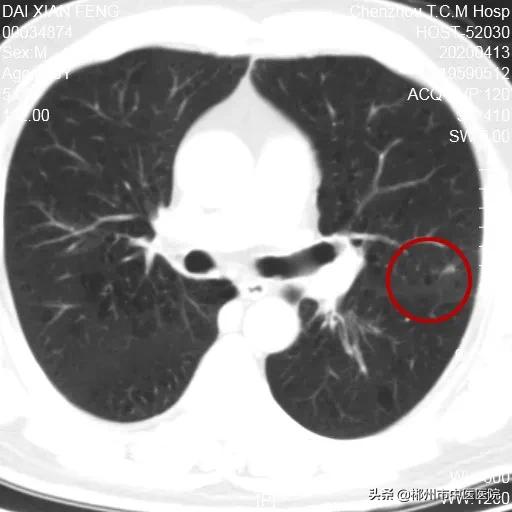

2020年4月13日5个月后第二次复查

残留区域进一步萎缩,考虑为疤痕组织形成

第二次复查残留区域5X3.4mm

通过复查可以发现,戴会长肺部的病灶明显消退呈瘢痕组织状态改变,并且肺功能无明显改变,对生活和工作也没有影响,可以说治疗取得了非常好的效果。